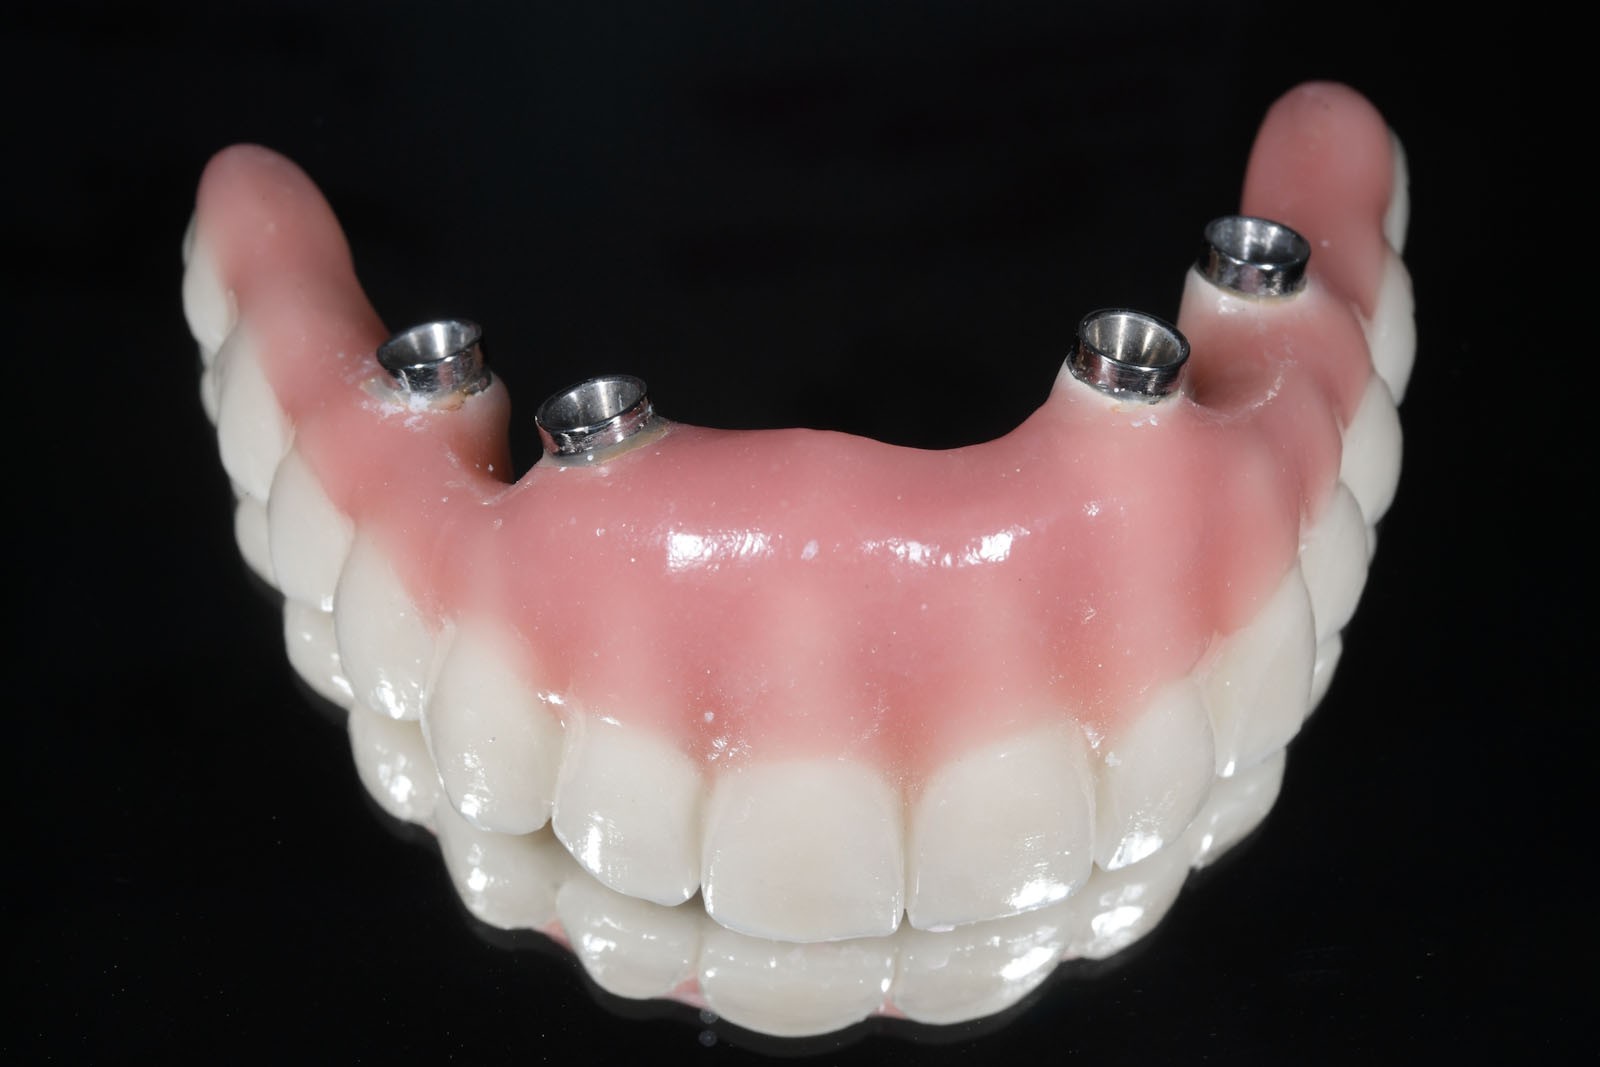

Do uzupełnień protetycznych ruchomych zalicza się protezy, które pacjent w dowolnym momencie może wyjmować z ust. Są to całkowite lub częściowe ruchome protezy akrylowe, nylonowe lub acetalowe oraz wykonane na bazie konstrukcji metalowej protezy szkieletowe. Wymienić tu należy również ruchome protezy typu overdenture wsparte na implantach.

W związku z ich użytkowaniem skala komfortu dla pacjenta zależy od tego, czy są to ruchome protezy Overdenture oparte jedynie na implantach, które poprawiają stabilizację protez zębowych, czy też na stałe mocowane na wszczepach mosty. W ślad za wyborem rodzaju mocowania protez idzie jakość odbudowy protetycznej. Protezy Overdenture są wykonane z materiału kompozytowego lub akrylu, natomiast mosty są wykonane z ceramiki.